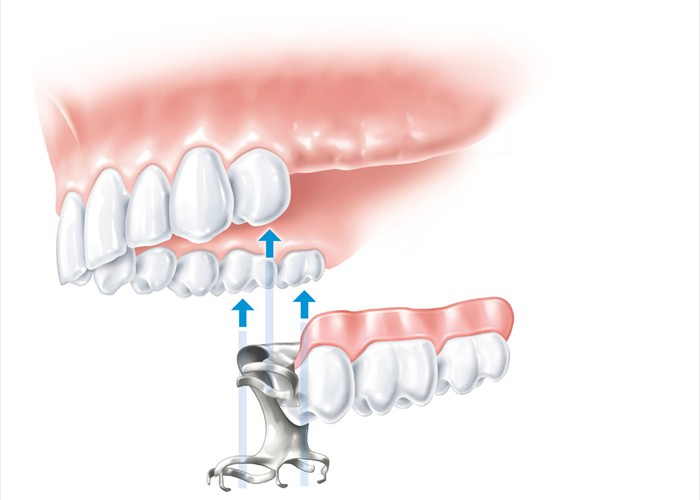

Engliederung einer Modellgussprothese zum Ersatz der drei hinteren Zähne

Engliederung einer Modellgussprothese zum Ersatz der drei hinteren Zähne